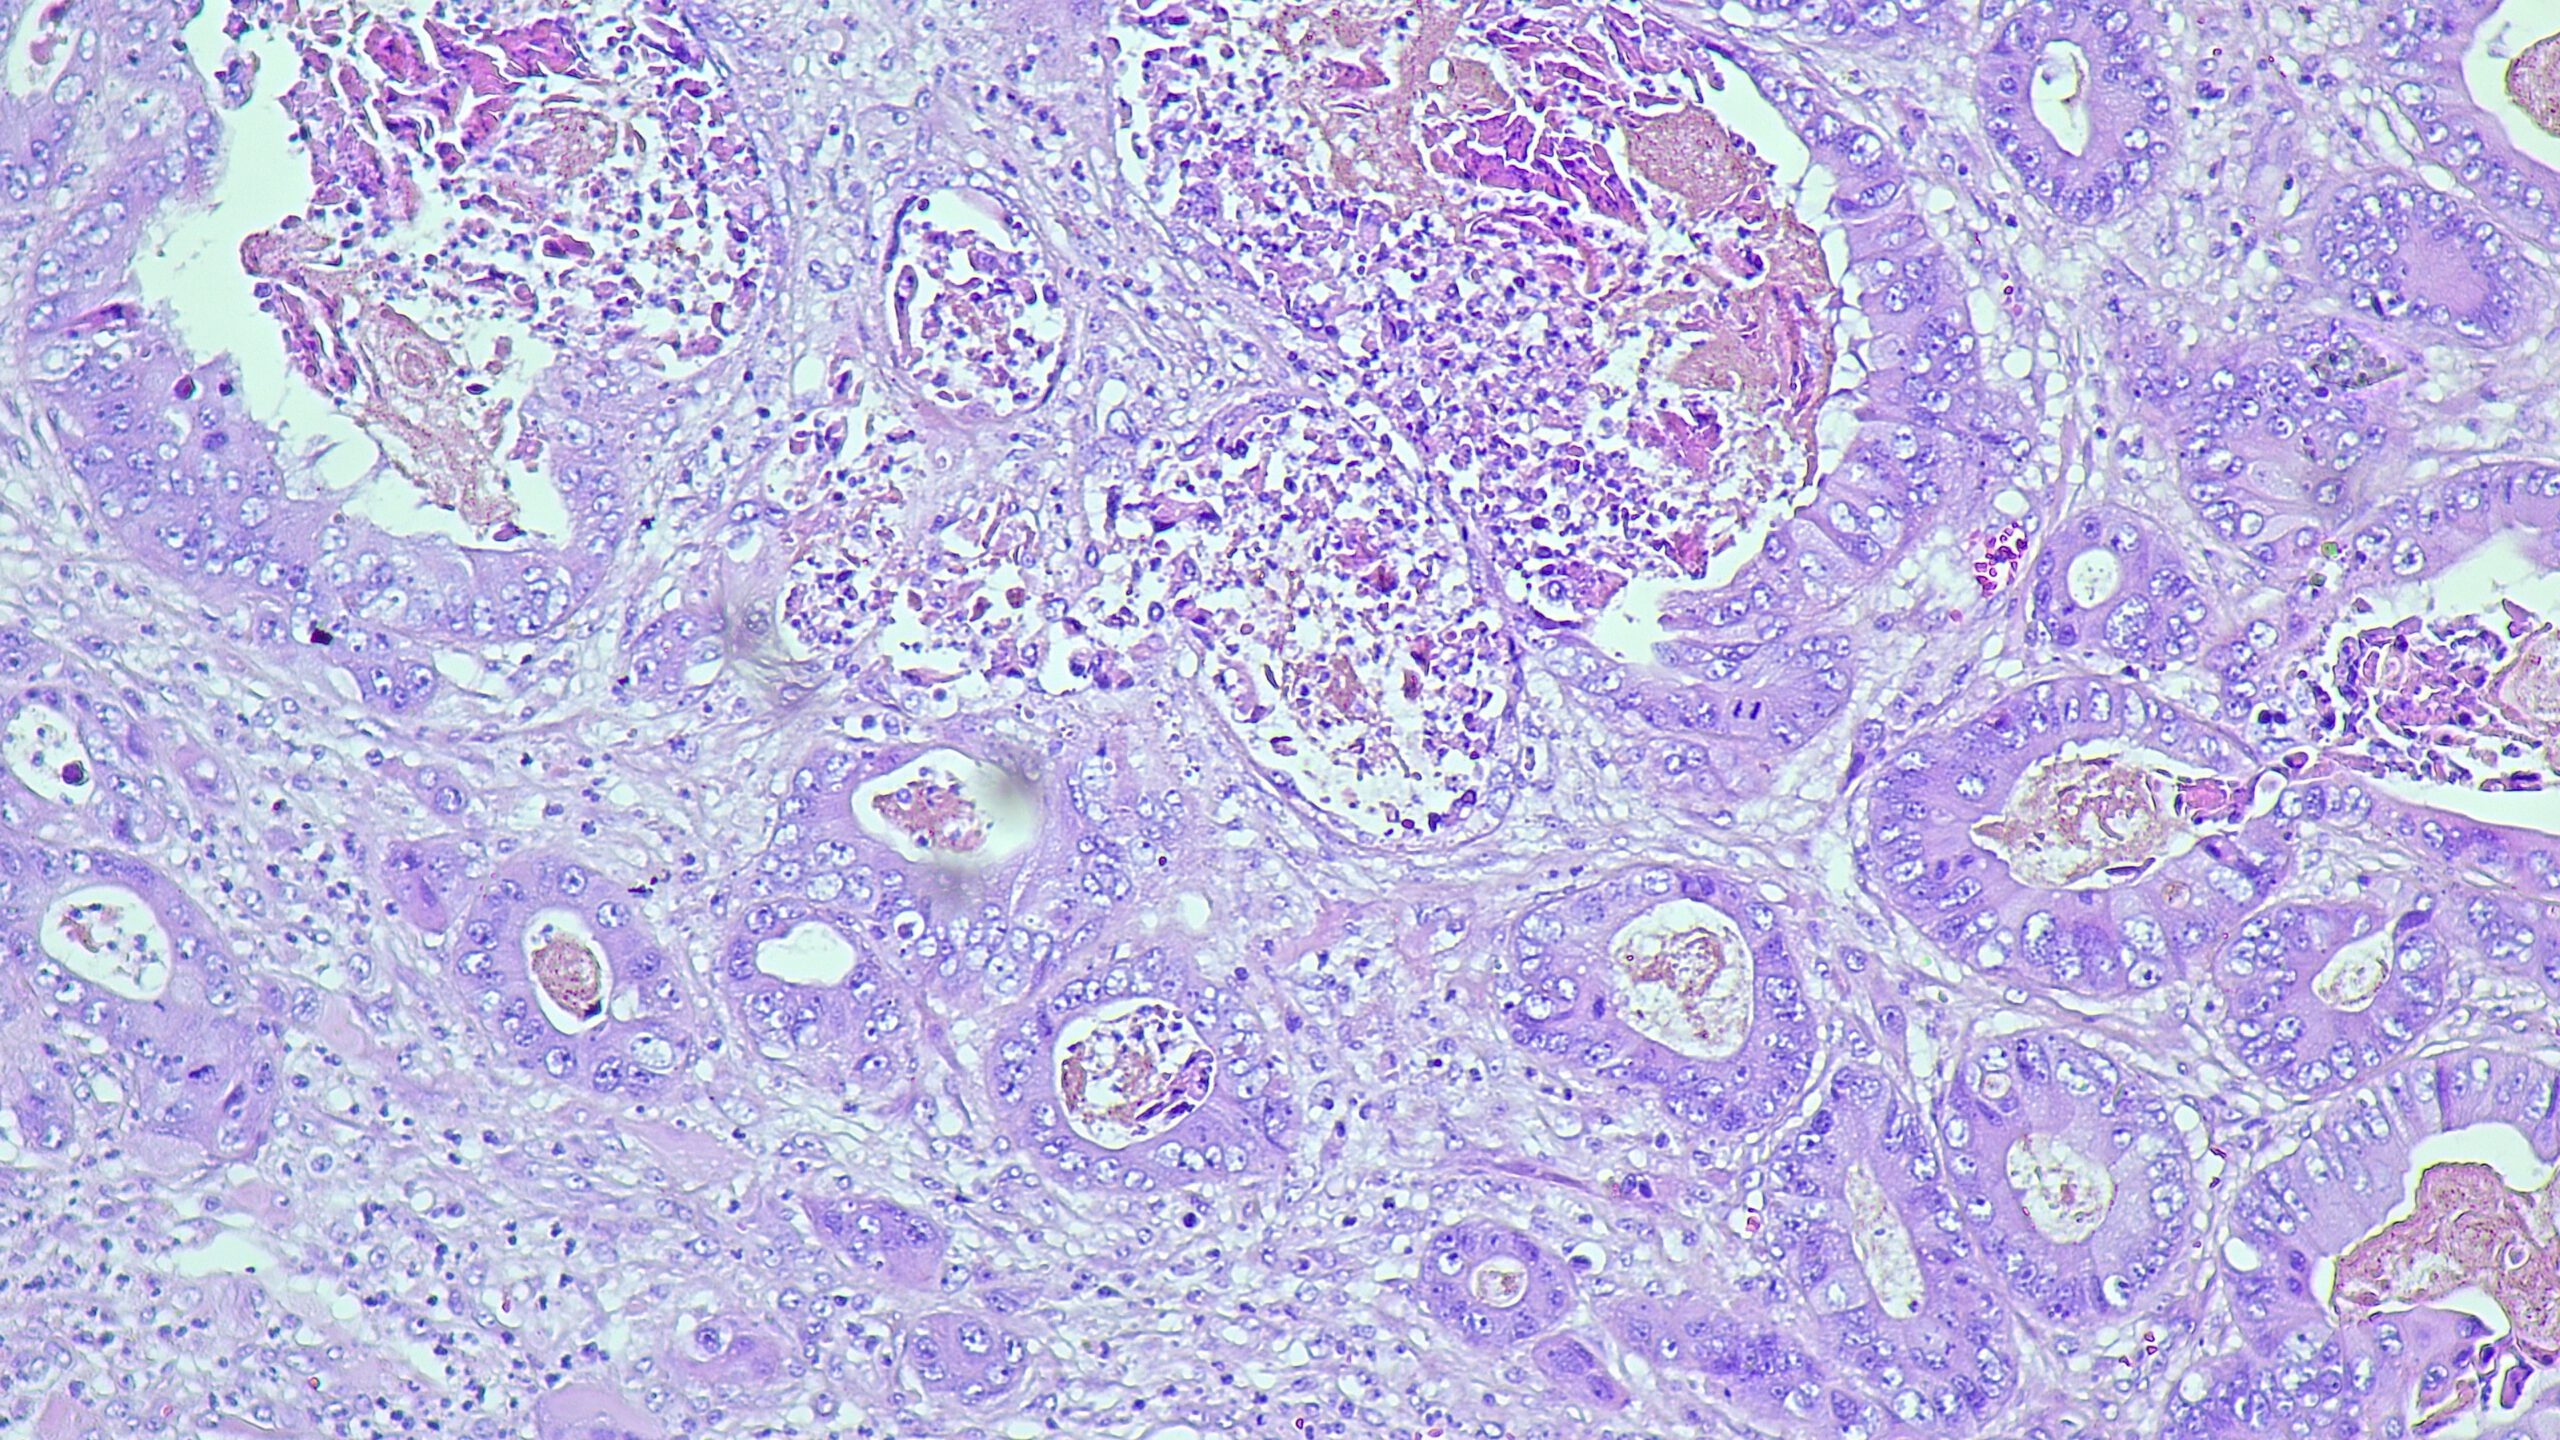

Selecting the optimal in vivo platform is critical for generating translatable oncology data. BioLegacy provides deep expertise across an extensive range of solid tumor models, from standard ectopic xenografts to complex orthotopic implantations that replicate the native tumor microenvironment. Our models include syngeneic models for immuno-oncology, humanized mice for evaluating biologics, and specialized assays like the hollow fiber model for early efficacy assessment, ensuring your therapeutic is tested in the most scientifically relevant system.